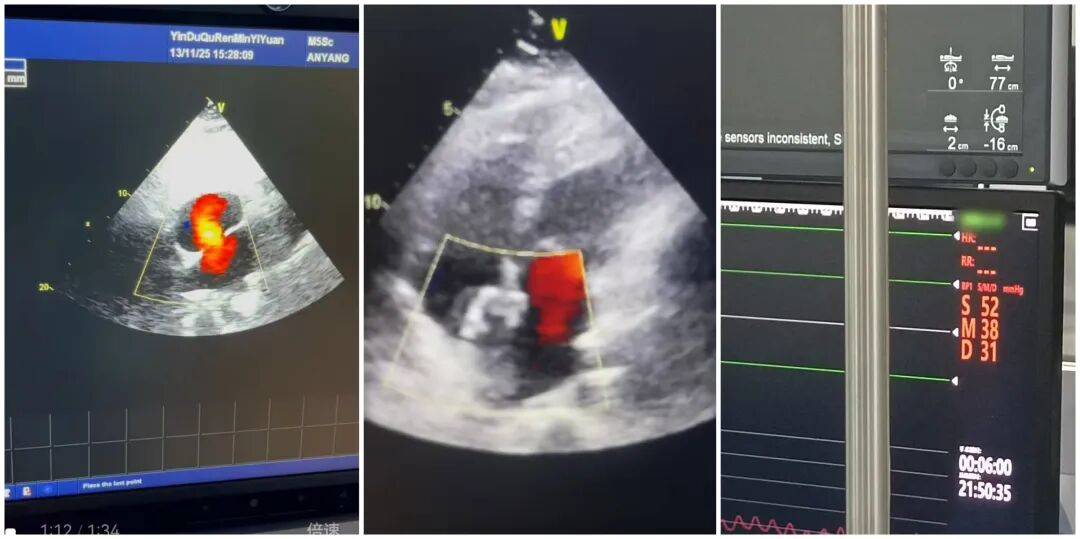

患者入院后,心血管内科团队高度重视,立即组织多学科会诊,结合心脏超声、心电图等详细检查结果,与特邀专家共同研判病情,制定了精准的个性化手术方案。11月14日手术当天,经右心导管检查显示,路女士的肺动脉压已高达52mmHg,需尽快干预。在团队的密切配合与专家的精准指导下,手术历时36分钟顺利完成,成功对其直径约25mm的室间隔缺损进行封堵。术后即刻超声检查证实,缺损处无过隔血流,手术效果达到预期。